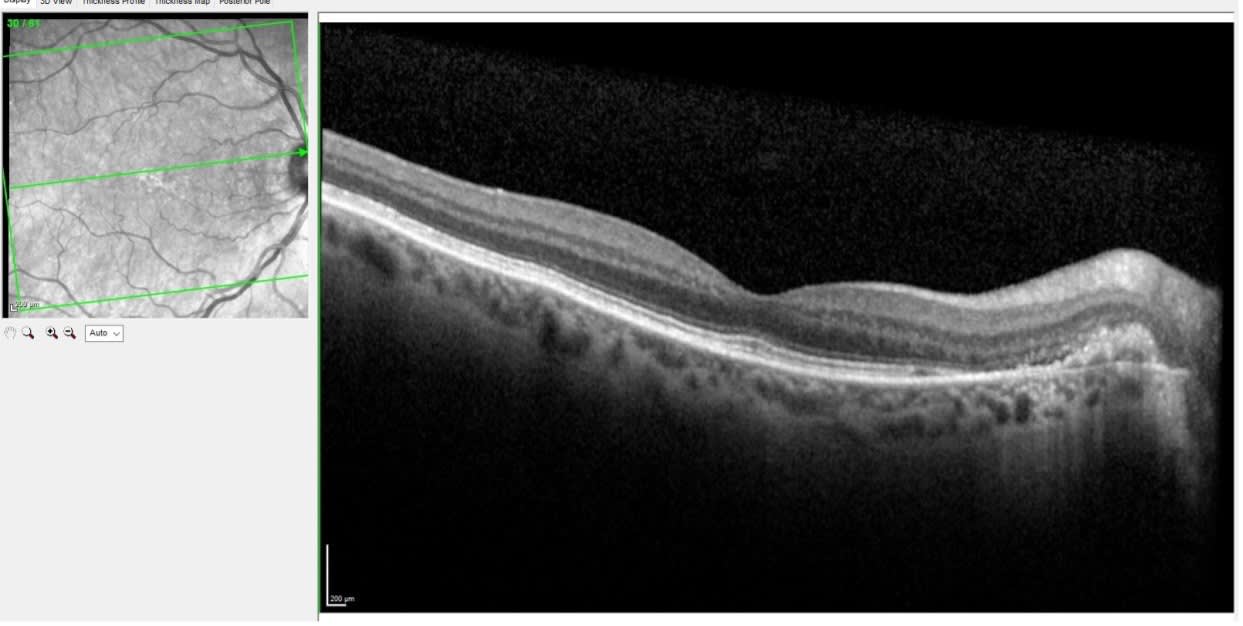

However, OCT scanning of the right macula told a different story, as seen in Figure 3.

On close examination of the OCT in the right eye, there is elevation of the neurosensory retina adjacent to the optic nerve, along with disruption of the retinal pigment epithelium (RPE) in this area, and sub-RPE turbid fluid. This finding is consistent with a peripapillary choroidal neovascular membrane.